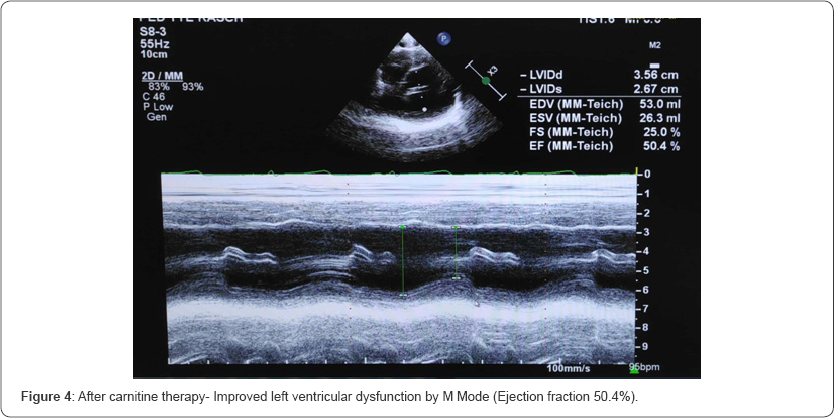

Her initial echocardiogram revealed severe depressed LV dysfunction- Ejection Fraction (EF) by modified Simpsons {24.3%}, M mode EF {24.2%} (Figure 1 &2). In relation to her hypertension related to end-stage renal failure, she is maintained on angiotensin-converting enzyme inhibitors. Further, she was investigated for carnitine levels which confirmed secondary carnitine deficiency (Table 1). After the 6 months trial of 20mg/kg of intravenous carnitine for 5 times a week (end of dialysis) leads to remarkable improvement in IH episodes and cardiac function. Her repeated echocardiogram revealed improved LV function- modified Simpsons {54.1%}, M mode EF {50.4%} (Figure 3 & 4).